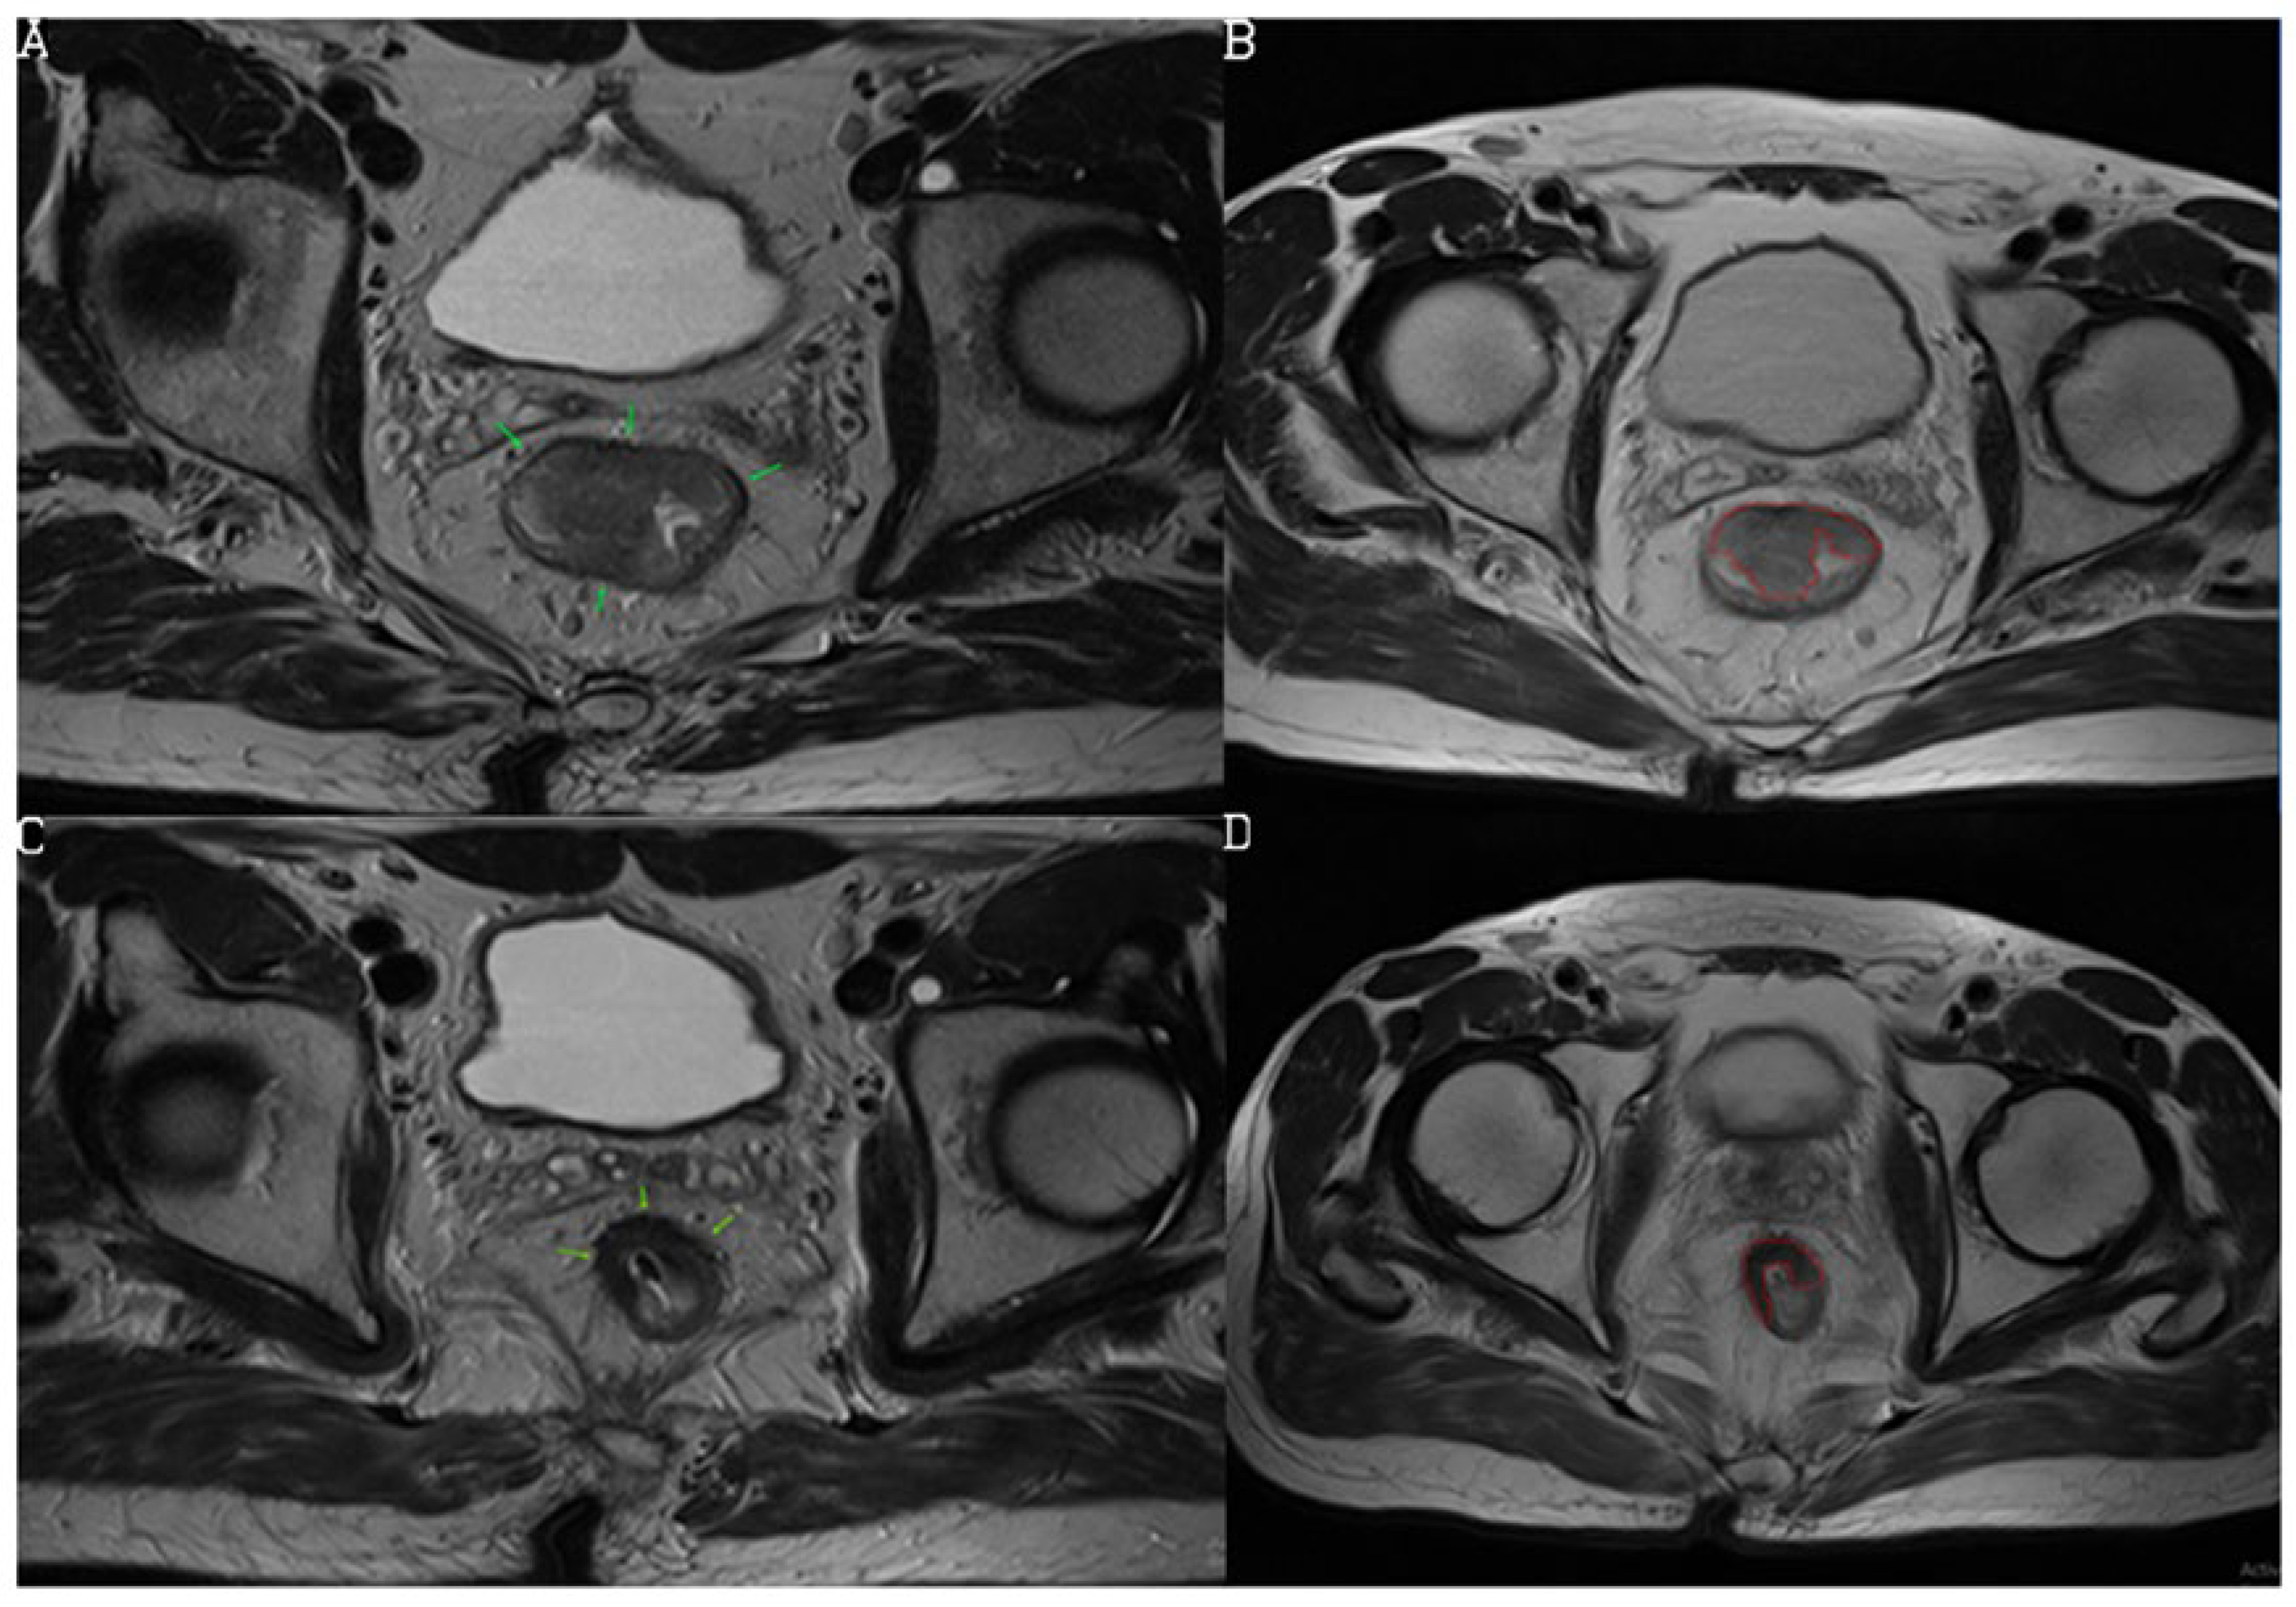

3.2. Diagnostic Performance of mrTRG